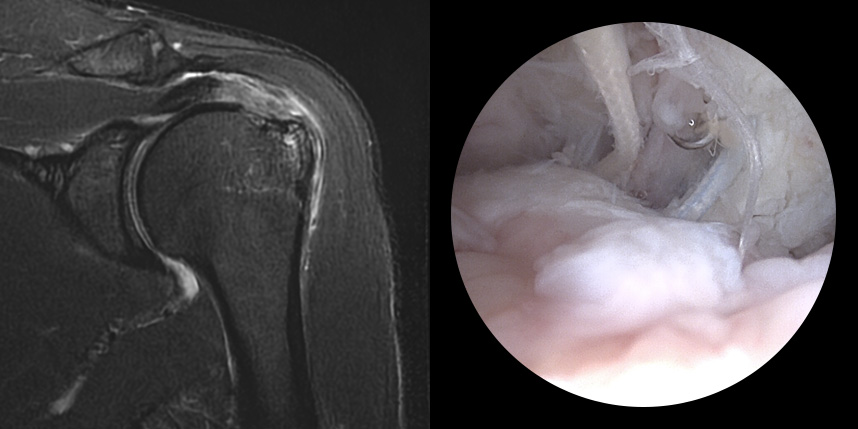

완전 파열시

브릿지 봉합술

힘줄이 약할 경우 재파열에 의한 재수술

패치 보강술